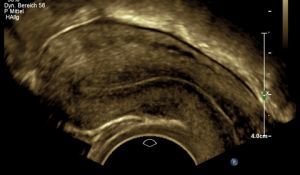

Uterus septiert

Unabdingbare Voraussetzung ist eine klare Beschreibung der Veränderungen, um die korrigierenden operativen Eingriffe bestmöglich planen und vorab besprechen zu können.

In den letzten Jahren hat sich hier die dreidimensionale Sonographie etabliert . In erfahrener Hand ist sie der vielerorts üblichen Kernspintomographie mindestens gleichwertig, in einigen Studien sogar überlegen.